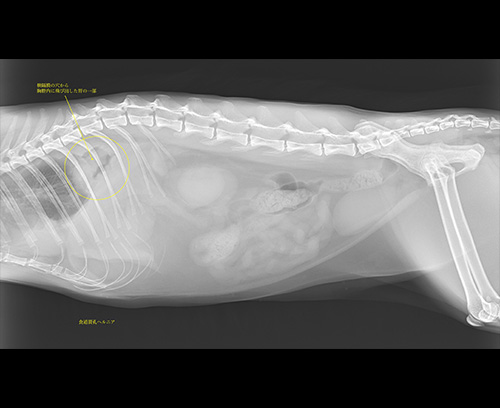

食道裂孔ヘルニア